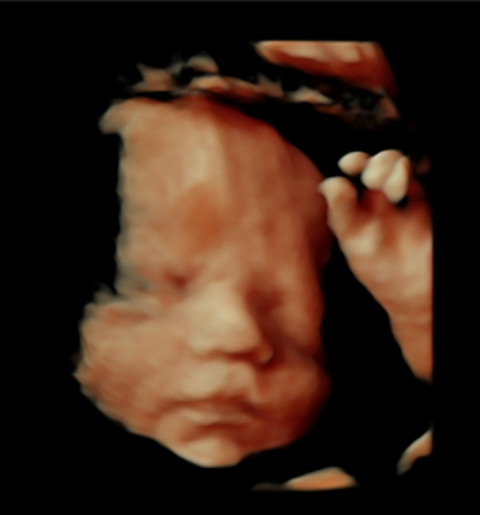

We offer elective 2D/3D/4D/5D pregnancy ultrasounds designed to create a calm, memorable experience for expecting families. These non-diagnostic scans allow you to bond with your baby and capture special moments in a comfortable, welcoming setting.

Gallery